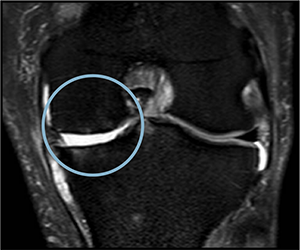

PRE TREATMENT

August 13, 2023

POST 2 APPLICATIONS

MAY 5, 2024